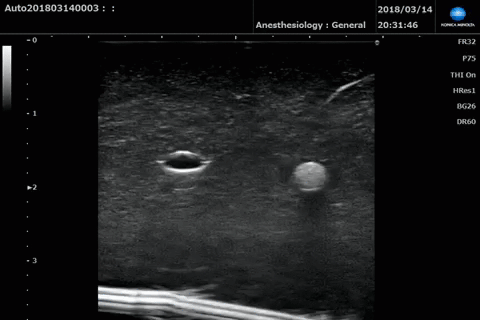

腹橫肌平面阻滯

(在腹內斜肌和腹橫肌之間可見蜂窩樣神經結構)